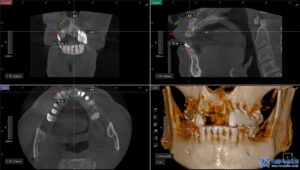

이 과정에서 환자분께

가장 적합한 방법인

무절개 임플란트로

치료를 진행하였습니다.

태평동치과 서울박사는 기본적으로

무절개 방식으로 임플란트를 진행하고 있으며,

이는 특히 당뇨가 있으시거나 고령으로 인해

상처 치유가 느린 분들께

권장되는 치료 방법입니다.

무절개 임플란트는 컴퓨터 분석을 통해

미리 계획된 경로를 따라 식립하기 때문에

절개가 필요하지 않고 출혈이 적으며

회복 속도가 빠릅니다.